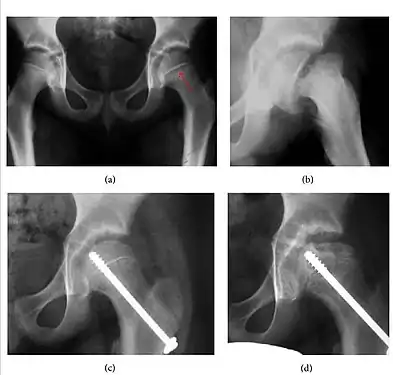

Slipped capital femoral epiphyses (SCFE)

Slipped capital femoral epiphyses (SCFE) usually affect 11- to 14-year-old adolescents (Figure 4). Radiographs may show widening and irregularity of the physis and posterior inferior displacement of the capital femoral epiphysis. On the AP view Klein’s line, tangent to the lateral aspect of the femoral neck, does not intersect the femoral head indicating that it is displaced. SCFE may compromise the blood supply to the femoral head and cause avascular necrosis, mainly when there is instability between the fragments.[1]